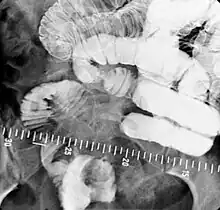

X-ray images are then taken in a supine position at intervals of 20–30 minutes. Real-time fluoroscopy is used to assess bowel motility. The radiologist may press or palpate the abdomen during images to separate intestinal loops. The total time necessary for the test depends on the speed of bowel motility or transit time and may vary between 1 and 3 hours.[17]

- Barium follow-through examinations are the most commonly used imaging technique in assessing patients with Crohn's disease, although CT and magnetic resonance imaging are widely accepted as being superior.[1] However Barium examinations remain superior in the depiction of mucosal abnormalities.[24] The features of Crohn's disease are well described by barium follow-through examinations, appearing as a typical "cobblestone pattern", but no information is obtained regarding extraluminal disease.[28] Radiographic imaging in Crohn's disease provides clinicians with objective evaluations of small bowel regions that are not accessible to standard endoscopic techniques.[29] Because of its length and complex loops, the small intestine is the most difficult part of the gastrointestinal tract to evaluate. Most endoscopic techniques are limited to the examination of proximal or distal segments, hence Barium follow-through remains in most centres the test of choice for the investigation of abdominal pain, diarrhoea and in particular diseases manifesting mucosal abnormalities such as coeliac and Crohn's disease.[26]